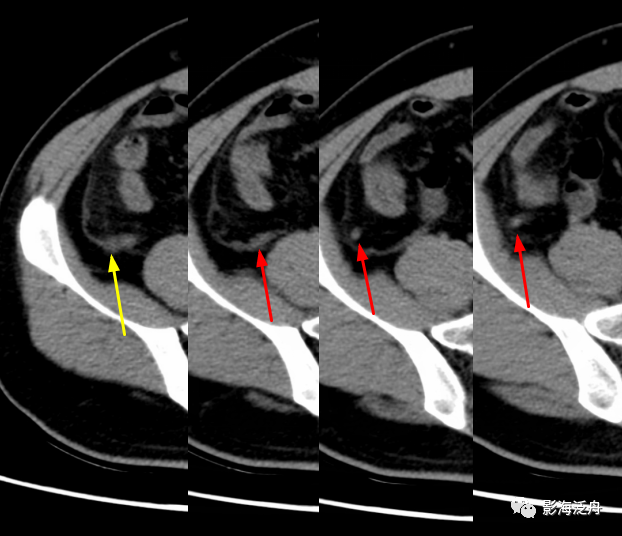

阑尾增粗,肿胀,阑尾口见粪石,周围脂肪间隙模糊,见索条影,曲面重建可

图片尺寸1080x444